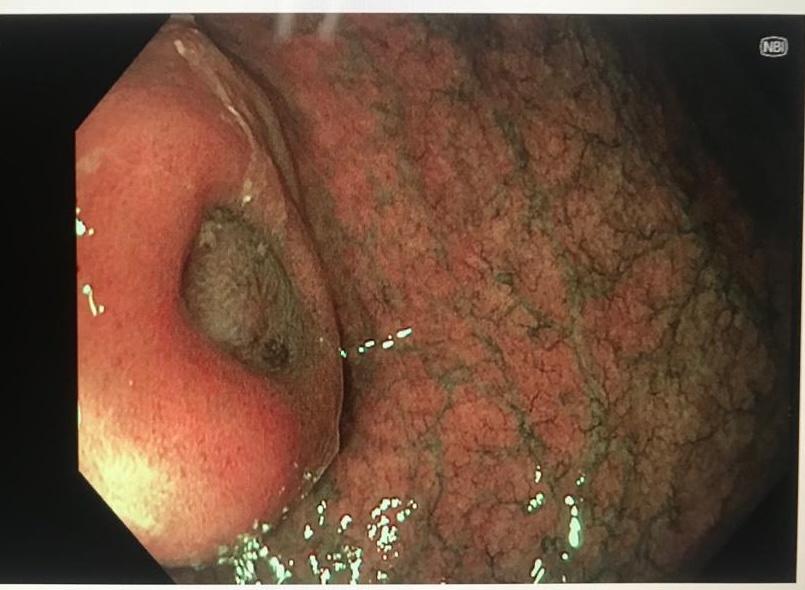

En chromoendoscopie virtuelle NBI, le tumeur est certaine